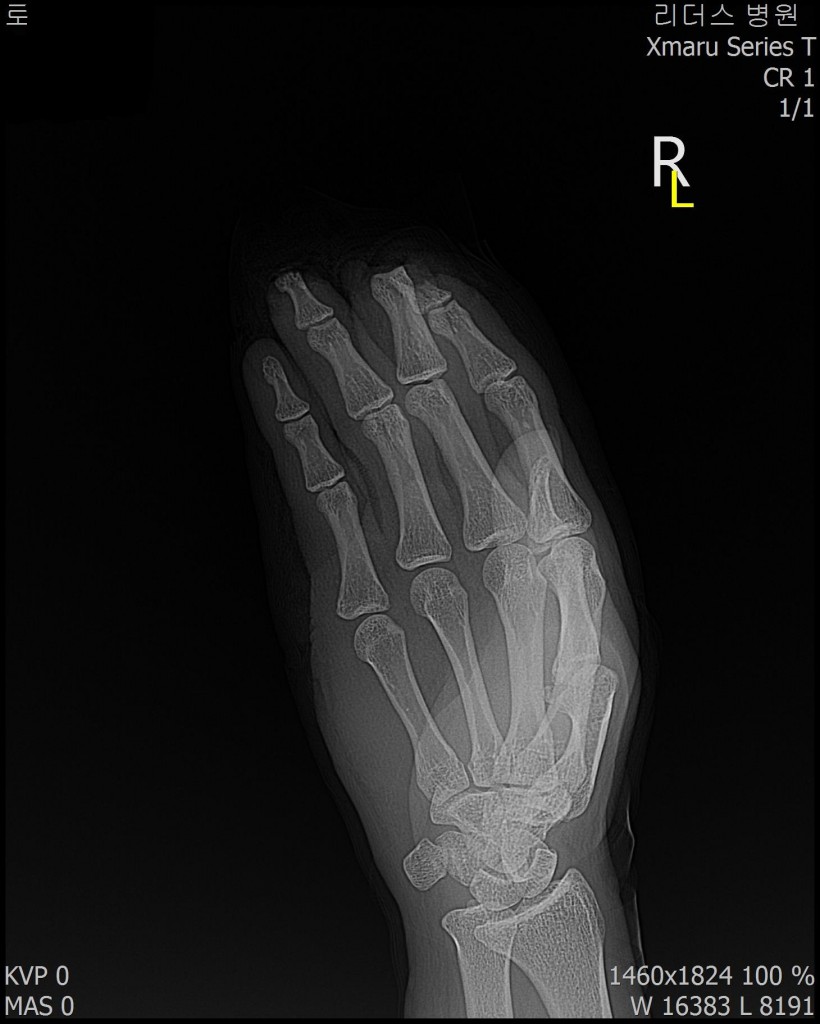

2018, 1월 1일 수지접합 ( 좌측 2,3,4수지 말단전달 치료 전, 후 모습)

2018 / 11일 당시 ( 외국인 로 **)께서 좌측 2,3,4수지 말단전달본원 방문하여